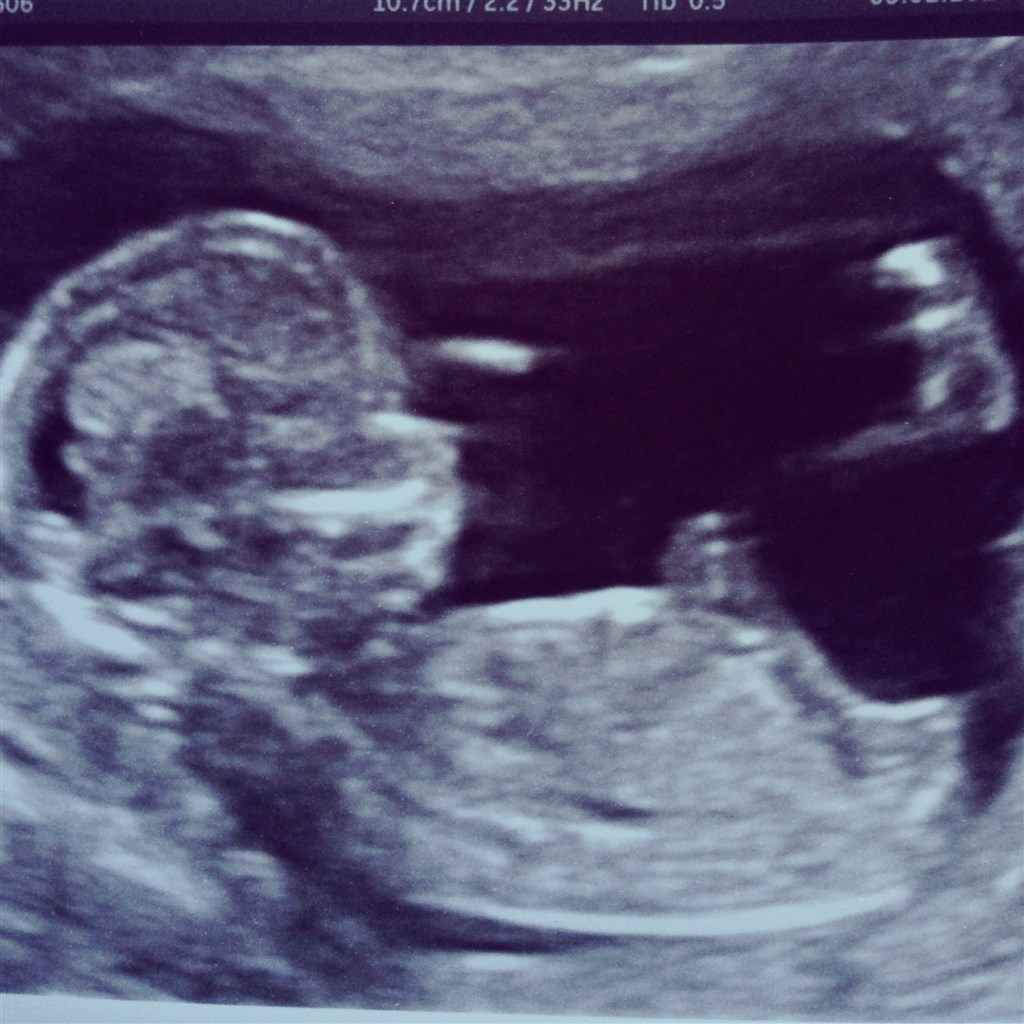

Babyen er 13+4 og har termin 9 august.

Kunde se en lille tap men jm ville ikke udtale sig om køn fordi de ligner hinanden nu.

så at fingrene var på plads og hjertelyden var fin ca 160 i minut

En stille og rolig baby inde i maven som laver små bevægelser. Glæder mig til at få køn at vide.